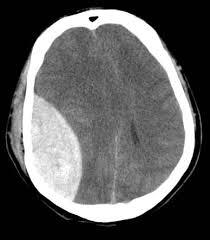

What is the following diagnosis?

Extradural haemorrhage

Why do extradural haemorrhage show up as a biconcave hyperattenuated area on CT?

Due to the insertion points of the dura to the suture lines of the skull